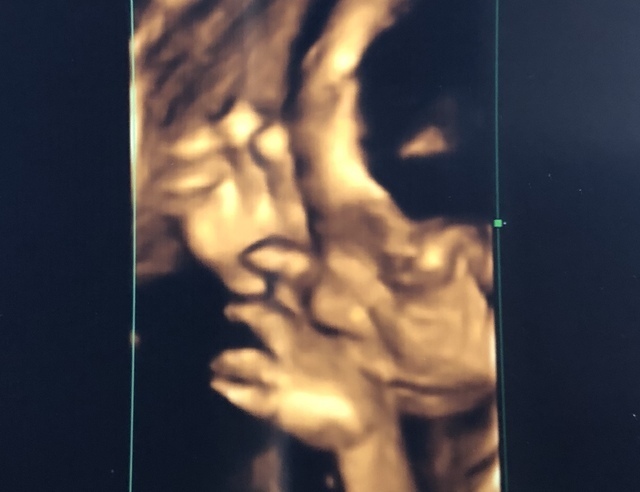

27週5日(27w5d・女の子)|bon420 さん(27歳)

エコー写真撮影時のエピソード:

初めてしっかり正面からお顔が見られた日。 こっちを向いて、お口をもぐもぐさせていました。手も近くにあったので、もしかしたら指しゃぶりをしようとしていたのかな~。

毎回頭の大きさ、お腹の大きさ、大腿骨の長さを測定してもらいますが、ちょっぴり頭が大きめだね、とのこと。元気に生まれてくれれば何でもいいよ♡ すくすく大きくなあれ♡